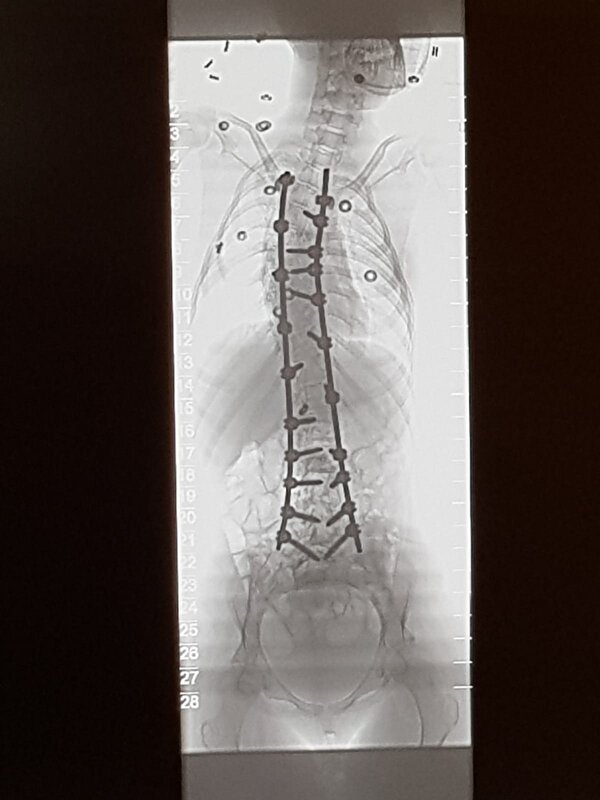

Hopelijk herstelt ze goed van haar zware operatie! Hoe lang gaat ze nog in het ziekenhuis liggen? Dan weet ik ongeveer hoeveel tijd ik nog heb om een kaartje te sturen